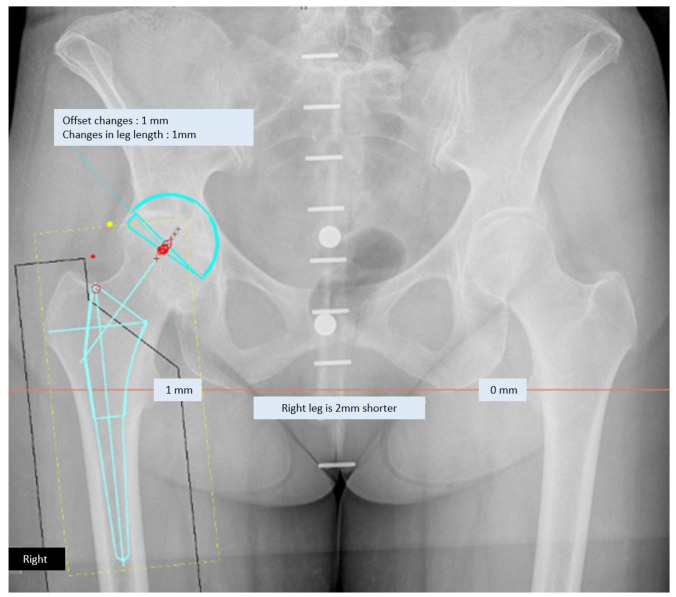

Materials and methods: A retrospective study was conducted. An analysis of 98 anteroposterior pelvic radiographs, which were individually templated by four surgeons (two hip surgeons and two orthopaedic residents) using TraumaCad® digital planning, was performed. A comparison of preoperatively planned sizes with implanted sizes was performed to evaluate the accuracy of predicting component size. The results of preoperative planning performed by hip surgeons and orthopaedic residents were compared for testing of the planner's experience.

Abstract Image